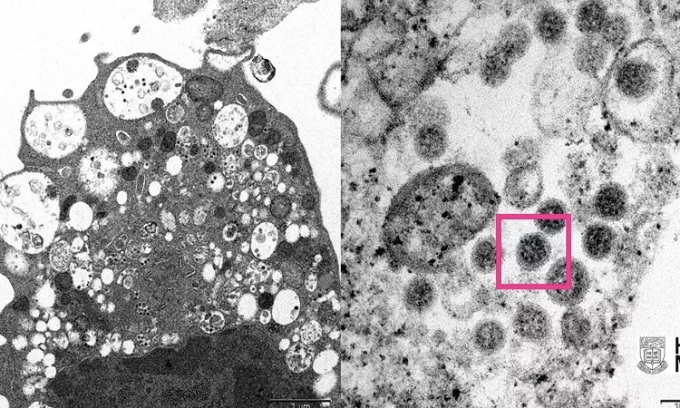

Hình ảnh của kháng thể mới dưới kính hiển vi

Chỉ có một kháng thể đã được cấp phép sử dụng ở bệnh nhân nhiễm virus không bị giảm nhiều khả năng vô hiệu hóa omicron trong phòng thí nghiệm. Đó là kháng thể mang tên sotrovimab. Kết quả nghiên cứu cho thấy tác dụng vô hiệu hóa chỉ giảm 2 - 3 lần đối với omicron.

Các thành viên trong những nhóm này nhắm vào một trong 4 khu vực đặc biệt ở gai protein không chỉ trên biến chủng nCoV mà cả nhóm virus corona liên quan gọi là sarbecovirus. Những khu vực này vẫn tồn tại bởi chúng thực hiện chức năng cơ bản có thể bị mất đi nếu đột biến.